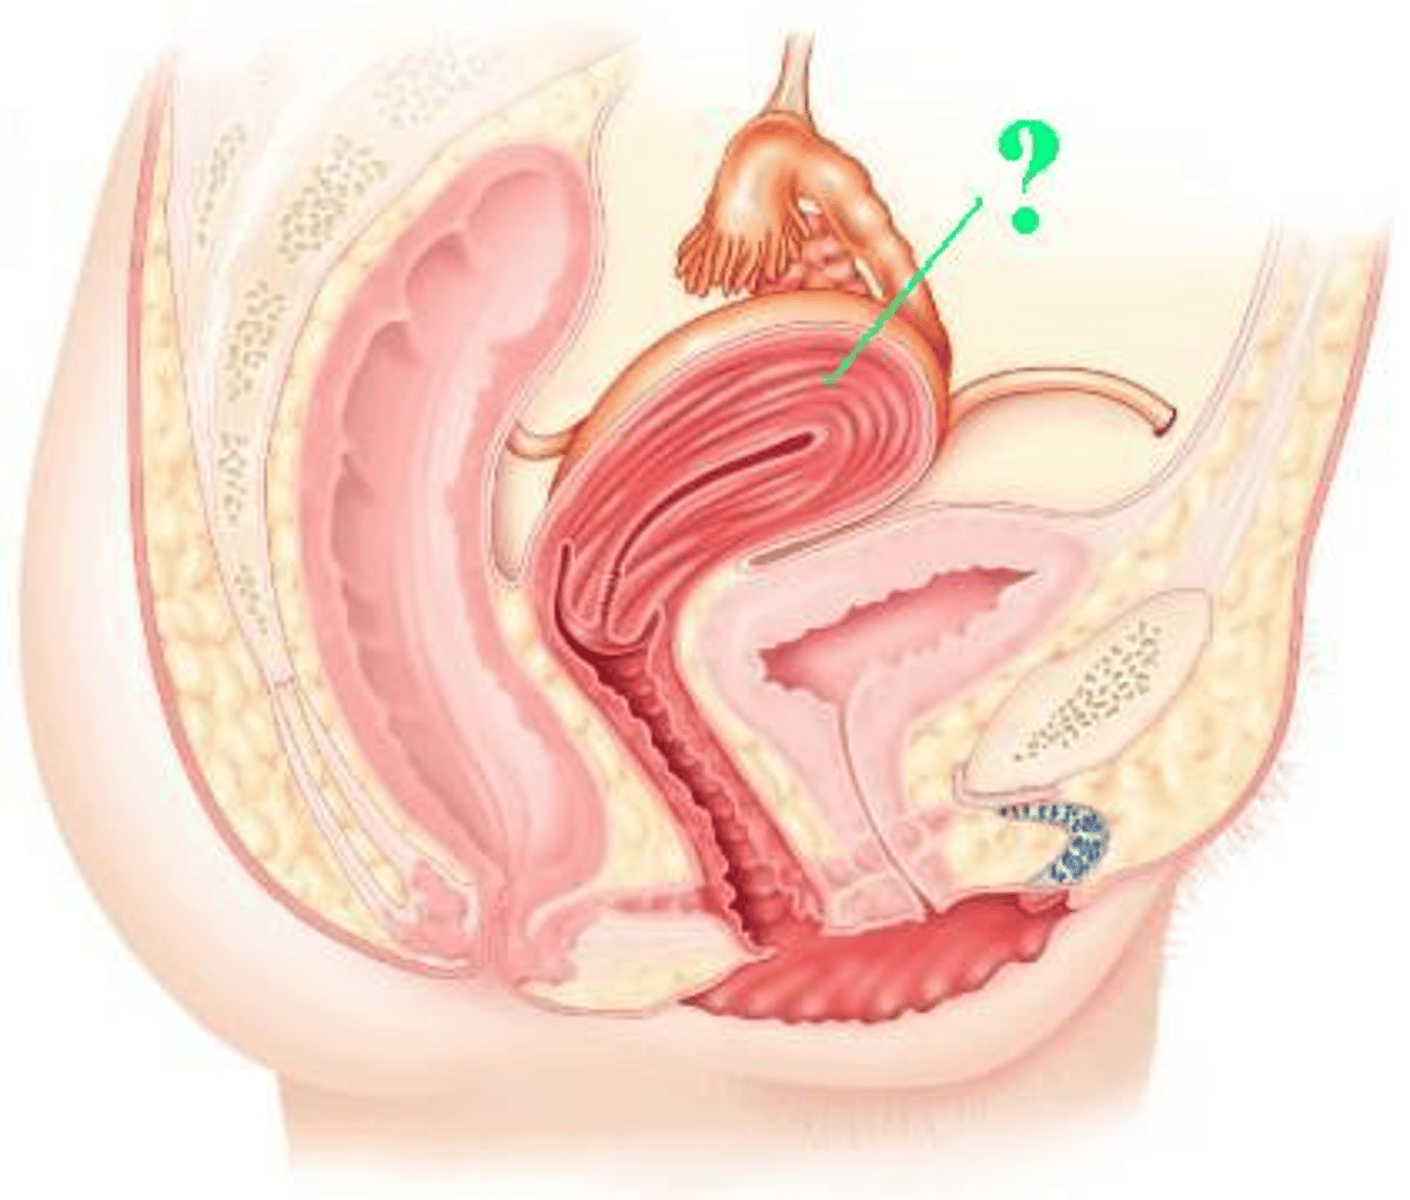

fallopian tube

Identify the indicated structure.

infundibulum